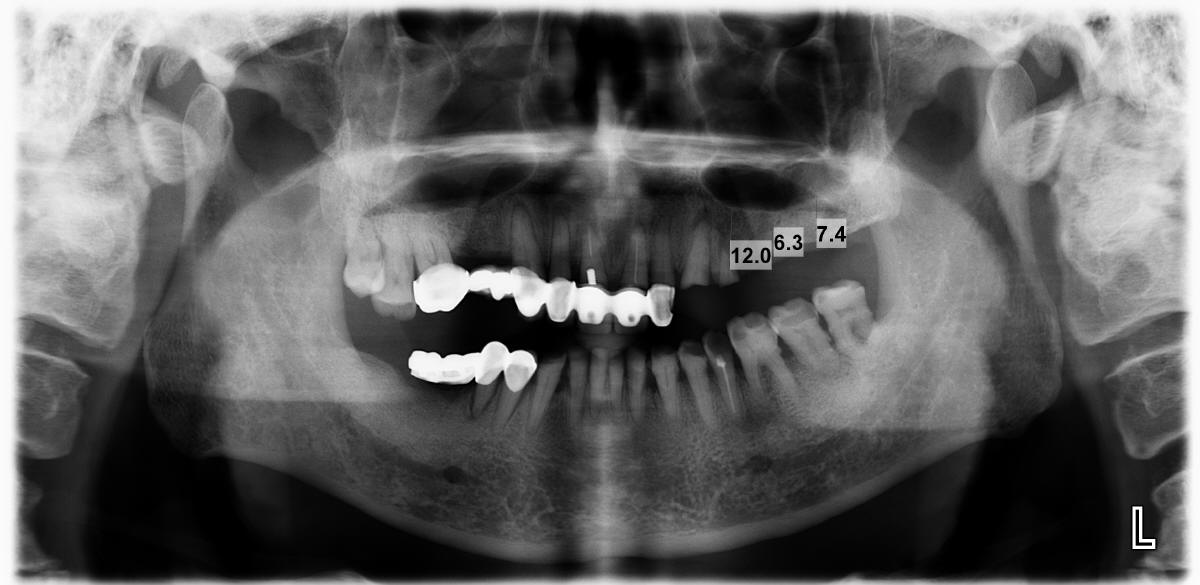

我有一个病人,80岁,糖尿病十年,目前用胰岛素控制,拟做种植,附图,听听同学的意见,请提供最详细的治疗方案,谢谢,咬合很紧,左侧缺牙间隙仅3毫米。汪贻静 Monday, July 8, 2013 4:13 AM

如果病人其他情况都好,左上三,四即刻植牙,下一次左上五,六植牙,建立第一磨牙咬合。以后必要时,除去右下桥,六号牙植牙。她骨头高度充足,可以做很多东西:植牙困难不大,但愿颊舌侧宽度好。